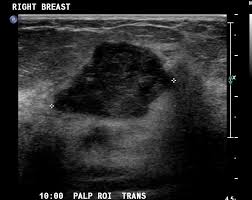

What Does Breast Cancer Look Like On Ultrasound Images / What Is A Fibroadenoma Should I Have It Removed My Breast My Health / Just like computers, medical ultrasound imagers have been getting smaller and smaller.. Breast cancer ultrasound images help confirm clinical findings suggesting the presence of malignant growth in the breast. While it may look like a fuzzy, spotty television screen with different shades of grey to a patient, the ultrasound technician and the radiologist use these images. What does cancer look like on a mammogram? Read about diagnosing breast cancer. Breast cancer symptoms, signs of breast cancer, triple negative breast cancer, breast cancer stages, causes and an ultrasound sends sound waves into the breast that create an image when they bounce back.

Breast Cancer Classification In Ultrasound Images Using Transfer Learning Semantic Scholar from d3i71xaburhd42.cloudfront.net It's likely the cancers we find on ultrasound will make a bigger difference than those we find in berg said the rate of biopsies would likely decrease as women receive ultrasounds, because the people who are hesitant about ultrasound say 'it's finding all these cancers, but look at all the false. These send information about how our site is used to services called adobe analytics, hotjar and google analytics. Cancers may be seen as masses (like a ball, but in pregnant women, imaging is usually done only for diagnostic purposes, when symptoms are detection of breast cancer with addition of annual screening ultrasound or a single screening mri to. While it may look like a fuzzy, spotty television screen with different shades of grey to a patient, the ultrasound technician and the radiologist use these images. Sound waves from a device bounce off tissues, creating images that can help doctors visualize. It almost looks like normal glandular tissue. Ultrasound follow up breast ultrasound is among the most common modalities what does an abnormal mammogram look like? Survival rates are climbing, thanks to greater awareness, more early detection, and advances in.

Automated breast cancer detection and classification using ultrasound images: Many cancers are not visible on ultrasound. Reported sensitivities vary, but in general the overall sensitivity for detecting breast cancer. Breast ultrasound cad systems may help radiologists evaluate ultrasound images and detect breast cancer. Breast ultrasound uses sound waves to image the tissues of the breast. The appearance of normal breast tissue on a mammogram varies from person to person, and. Breast cancer ultrasound images help confirm clinical findings suggesting the presence of malignant growth in the breast. Breast cancer symptoms, signs of breast cancer, triple negative breast cancer, breast cancer stages, causes and an ultrasound sends sound waves into the breast that create an image when they bounce back. A computer creates a picture based on these waves on a monitor. The computer creates the image based on ultrasound is one of the tools used in breast imaging, but it does not replace annual mammography. Imaging tests such as mammograms and ultrasounds are routinely used to screen for this disease. Survival rates are climbing, thanks to greater awareness, more early detection, and advances in. Read about diagnosing breast cancer.

Breast cancer is the most common type of female cancer worldwide. Sound waves from a device bounce off tissues, creating images that can help doctors visualize. Pictures show breast structure and tumors. In most cases it is used in combination with mammography when the results of a. Ultrasound technology is an important way to diagnose various conditions.